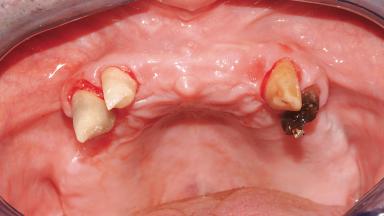

Immediate Loading of Six Implants in the Maxilla and Final Restoration with a Full-Arch Gold/Ceramic FDP Involving the Concept of Tilted Implants

A 61-year-old male patient with a failing fixed maxillary rehabilitation and a fixed mandibular rehabilitation requested a new fixed maxillary rehabilitation. The patient was wearing a temporary metal-reinforced maxillary bridge inserted two years before the consultation. He reported that his previous dentist did not want to insert a definitive framework because he considered the residual teeth to have a negative prognosis. The patient reported a history of recurrent caries and endodontic complications as the main reason for the previous extractions. The anamnesis was negative for periodontal disease and bruxism. The patient’s chief compliant was the mobility of his maxillary prosthesis, which needed to be re-cemented frequently, and discomfort during chewing.Moreover, the patient was not satisfied with the esthetic appearance of his maxillary teeth, which he found too long. The patient asked for a stable and comfortable fixed maxillary rehabilitation and firmly rejected any removable solution.

Soft Tissue Anatomy Intact Defective

Bone Volume Horizontally and vertically sufficient Horizontally deficient Deficient vertically or deficient vertically AND horizontally